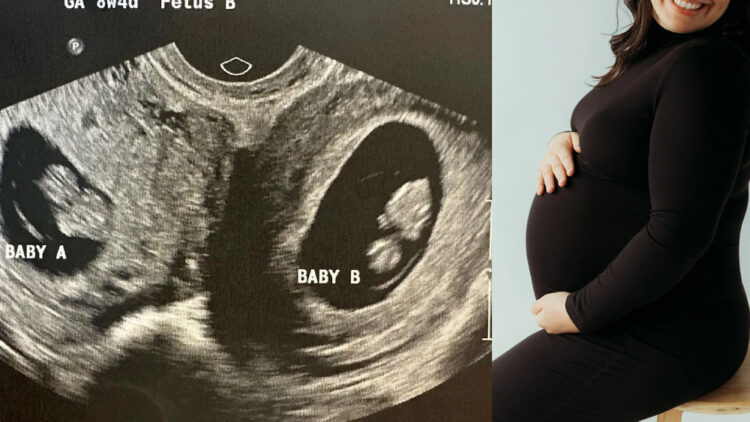

ഇരട്ടകുട്ടികൾക്ക് ജന്മം നൽകുന്നതിൽ പുതുമയൊന്നുമില്ല, എന്നാൽ ചൈനയിൽ റിപ്പോർട്ട് ചെയ്ത ഇരട്ടപ്രസവം സോഷ്യൽ മീഡിയയിൽ വലിയ ചർച്ചയാവുകയാണ്. കാരണം ഈ കുട്ടികൾ ജനിച്ചുവീണത് ഒരു ഗർഭപാത്രത്തിൽ നിന്നായിരുന്നില്ല. അപൂർവങ്ങളിൽ അപൂർവമായി കണ്ടുവരുന്ന ഒരു സവിശേഷത ആ ചൈനീസ് സ്ത്രീക്കുണ്ടായിരുന്നു. രണ്ട് ഗർഭപാത്രങ്ങളുള്ള യുവതി ഓരോന്നിലും ഓരോ കുഞ്ഞിനെ വീതമാണ് എട്ടരമാസക്കാലം പേറിയത്.

ചൈനയിലെ വടക്കുപടിഞ്ഞാറൻ മേഖലയിലെ ഷാൻസി പ്രവിശ്യയിൽ നിന്നുള്ള ലി എന്ന യുവതിയാണ് അപൂർവ പ്രസവത്തിന് വിധേയയായത്. ലോകത്തിലെ 0.3 ശതമാനം സ്ത്രീകളിൽ മാത്രം കണ്ടുവരുന്ന uterus didelphys എന്ന അവസ്ഥയായിരുന്നു ലി എന്ന യുവതിക്ക്. രണ്ട് പൂർണ ഗർഭപാത്രങ്ങളാണ് യുവതിക്കുള്ളത്. ഓരോന്നിനും പ്രത്യേകം അണ്ഡാശയങ്ങളുമുണ്ട്. രണ്ട് ഗർഭപാത്രങ്ങളിലും കുഞ്ഞുങ്ങളെ ചുമന്ന ലീ, ഒരാൺകുഞ്ഞിനും ഒരു പെൺകുഞ്ഞിനും ജന്മം നൽകി.

സിസേറിയനിലൂടെയാണ് കുഞ്ഞുങ്ങളെ പുറത്തെടുത്തത്. ആൺകുഞ്ഞ് 3.3 കിലോയും പെൺകുഞ്ഞ് 2.4 കിലോയും തൂക്കമുണ്ടായിരുന്നു. രണ്ട് കുഞ്ഞുങ്ങളുടെയും ആരോഗ്യനില തൃപ്തികരമാണെന്ന് ഡോക്ടർമാർ വ്യക്തമാക്കി. ദശലക്ഷത്തിൽ ഒരാൾക്ക് മാത്രമേ ഇതുപോലെ പ്രസവിക്കാൻ കഴിയൂവെന്ന് ലിയെ ചികിത്സിച്ച ഡോക്ടർമാർ പറയുന്നു. ലിയുടെ രോഗാവസ്ഥയിലുള്ള ഒരാൾക്ക് സ്വാഭാവികമായി ഗർഭം ധരിക്കാൻ പ്രയാസമാണ്. എന്നാൽ ഡോക്ടർമാരുടെ ഇടപെടലുകൾ ഇല്ലാതെയാണ് ലി ഗർഭിണിയായത്. ഇതിന് മുൻപും ഇവർ ഗർഭിണിയായിരുന്നു. എന്നാൽ ഏതാനും ആഴ്ചകൾ പിന്നിട്ടപ്പോൾ ഗർഭസ്ഥ ശിശുവിനെ നഷ്ടപ്പെട്ടു. രണ്ടാമത് ഗർഭിണി ആയപ്പോൾ വളരെ ശ്രദ്ധയോടെയാണ് ലീയെ ഡോക്ടർമാർ പരിപാലിച്ചത്. ഒടുവിൽ ആരോഗ്യമുള്ള രണ്ട് കുഞ്ഞുങ്ങൾക്ക് ജന്മം നൽകുകയായിരുന്നു യുവതി.